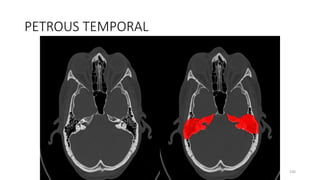

PETROUS PART OF TEMPORAL BONE

PETROUS TEMPORAL